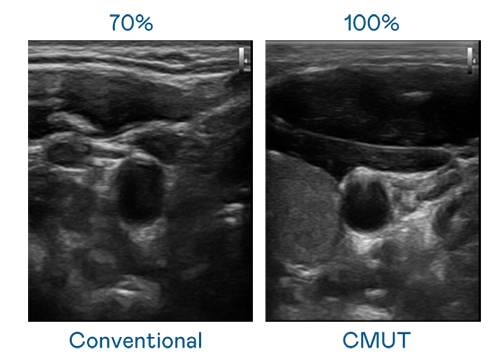

CMUT 技术是一种用电容式微机电元件来产生超音波讯号的技术。与传统 PZT 压电式技术相比,CMUT 频宽增加 30%,更宽频的超音波讯号让影像解析度大幅提升,是实现高影像品质医疗超音波扫描、促进精准医疗发展的关键技术。

超音波影像的解析度高低,首先取决于探头能发出的讯号频宽。Ebpay CMUT 可提供高清晰的超音波讯号,提供高频宽、高灵敏度、影像纹理细节更高的超音波影像,协助医护人员缩短影像判读时间及利用精准的医疗影像进行诊断。